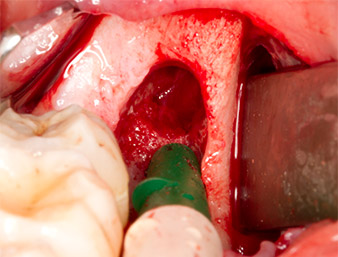

To obtain autogenous material for subsequent wound treatment, healthy bone chips were harvested from the surroundings of the root remnant with a piezo surgical instrument (Piezomed B5) (Fig. 5).

The autogenous tissue was removed with the scraper-shaped section of the working part of the instrument and stored in a physiological saline solution until further use (cf. Fig. 13).